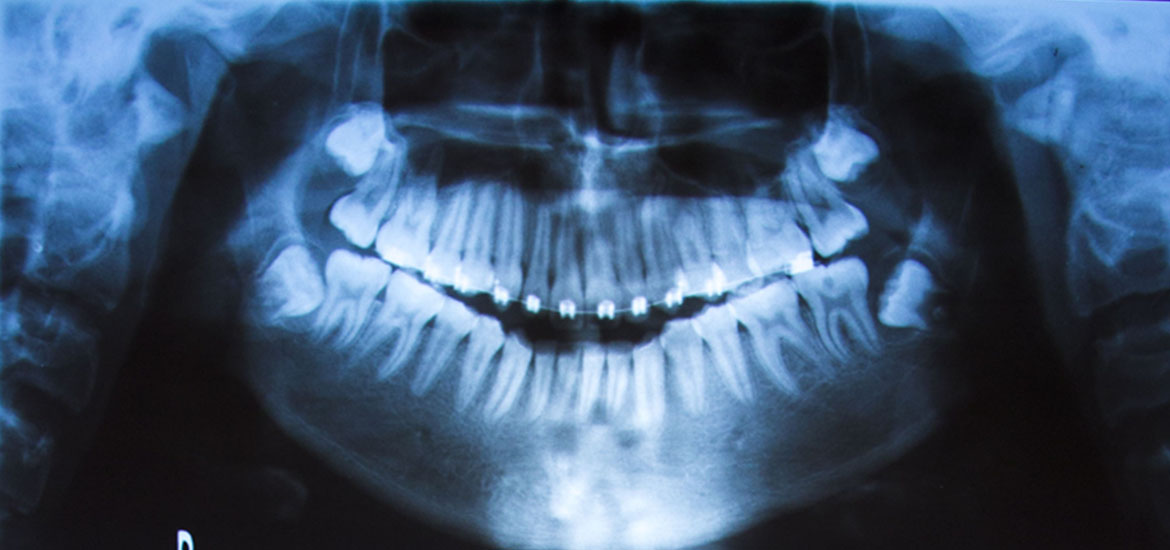

Cuando una pieza dentaria se encuentra muy comprometida, y cuando se descartó la posibilidad de otro tratamiento como la endodoncia y la prótesis fija, procedemos a la extracción dentaria de quien está encargada la Cirugía Bucal.

Esta especialidad también está encargada de realizar cirugías menores, como la extracción de piezas dentarias retenidas.